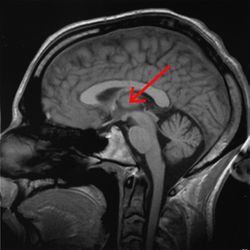

| مقطع صورة رنين مغناطيسي لمخ بشري, المهاد مبين فيه. | ||

المهاد Thalamus (من اليونانية θάλαμος = المهد أو المخدع, غرفة) هو زوج وجزء متماثل في المخ. وتشكل الجزء الرئيسي من diencephalon.

تعتبر الوظيفة الأساسية لمنطقة المهاد هي الإحساس و يتحكم في الحركة البدنية، و يعتبر كمحطة للإشارات الحسية التي تصل إلى قشرة المخ و يعمل كمركز لتفسير بعض منها، مثل الألم و الشعور بالحرارة و الضغط واللمس. [1]